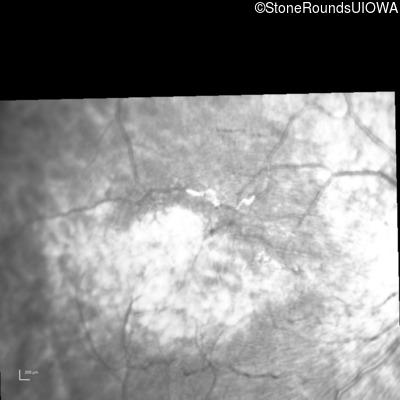

Infrared Fundus Photograph - Left - 20/80 -1

Exemplar